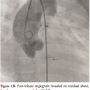

After confirming precise position of the device on transthoracic echocardiography and control angiography, the rest of the device was deployed on the pulmonary arterial side, by withdrawing the delivery sheath. Post-release angiogram revealed no residual shunt. However, there was new grade I mild AR (Figure 1B) that was also confirmed on color doppler echocardiography (Figure 2). Clinically no murmur was audible and aortic pulse pressure had decreased as well as pulmonary artery pressure (Aortic pressure 112/72 mmHg; pulmonary artery pressure 40/25 mmHg; mean 33 mmHg). As the defect was remote from aortic valve and there was no impingement on it, the result was accepted. On follow-up at 3 months and 6 months, patient was asymptomatic. Importantly, there was a progressive decrease in the grade of AR from mild to only trivial grade at 6 months (Figure 3).